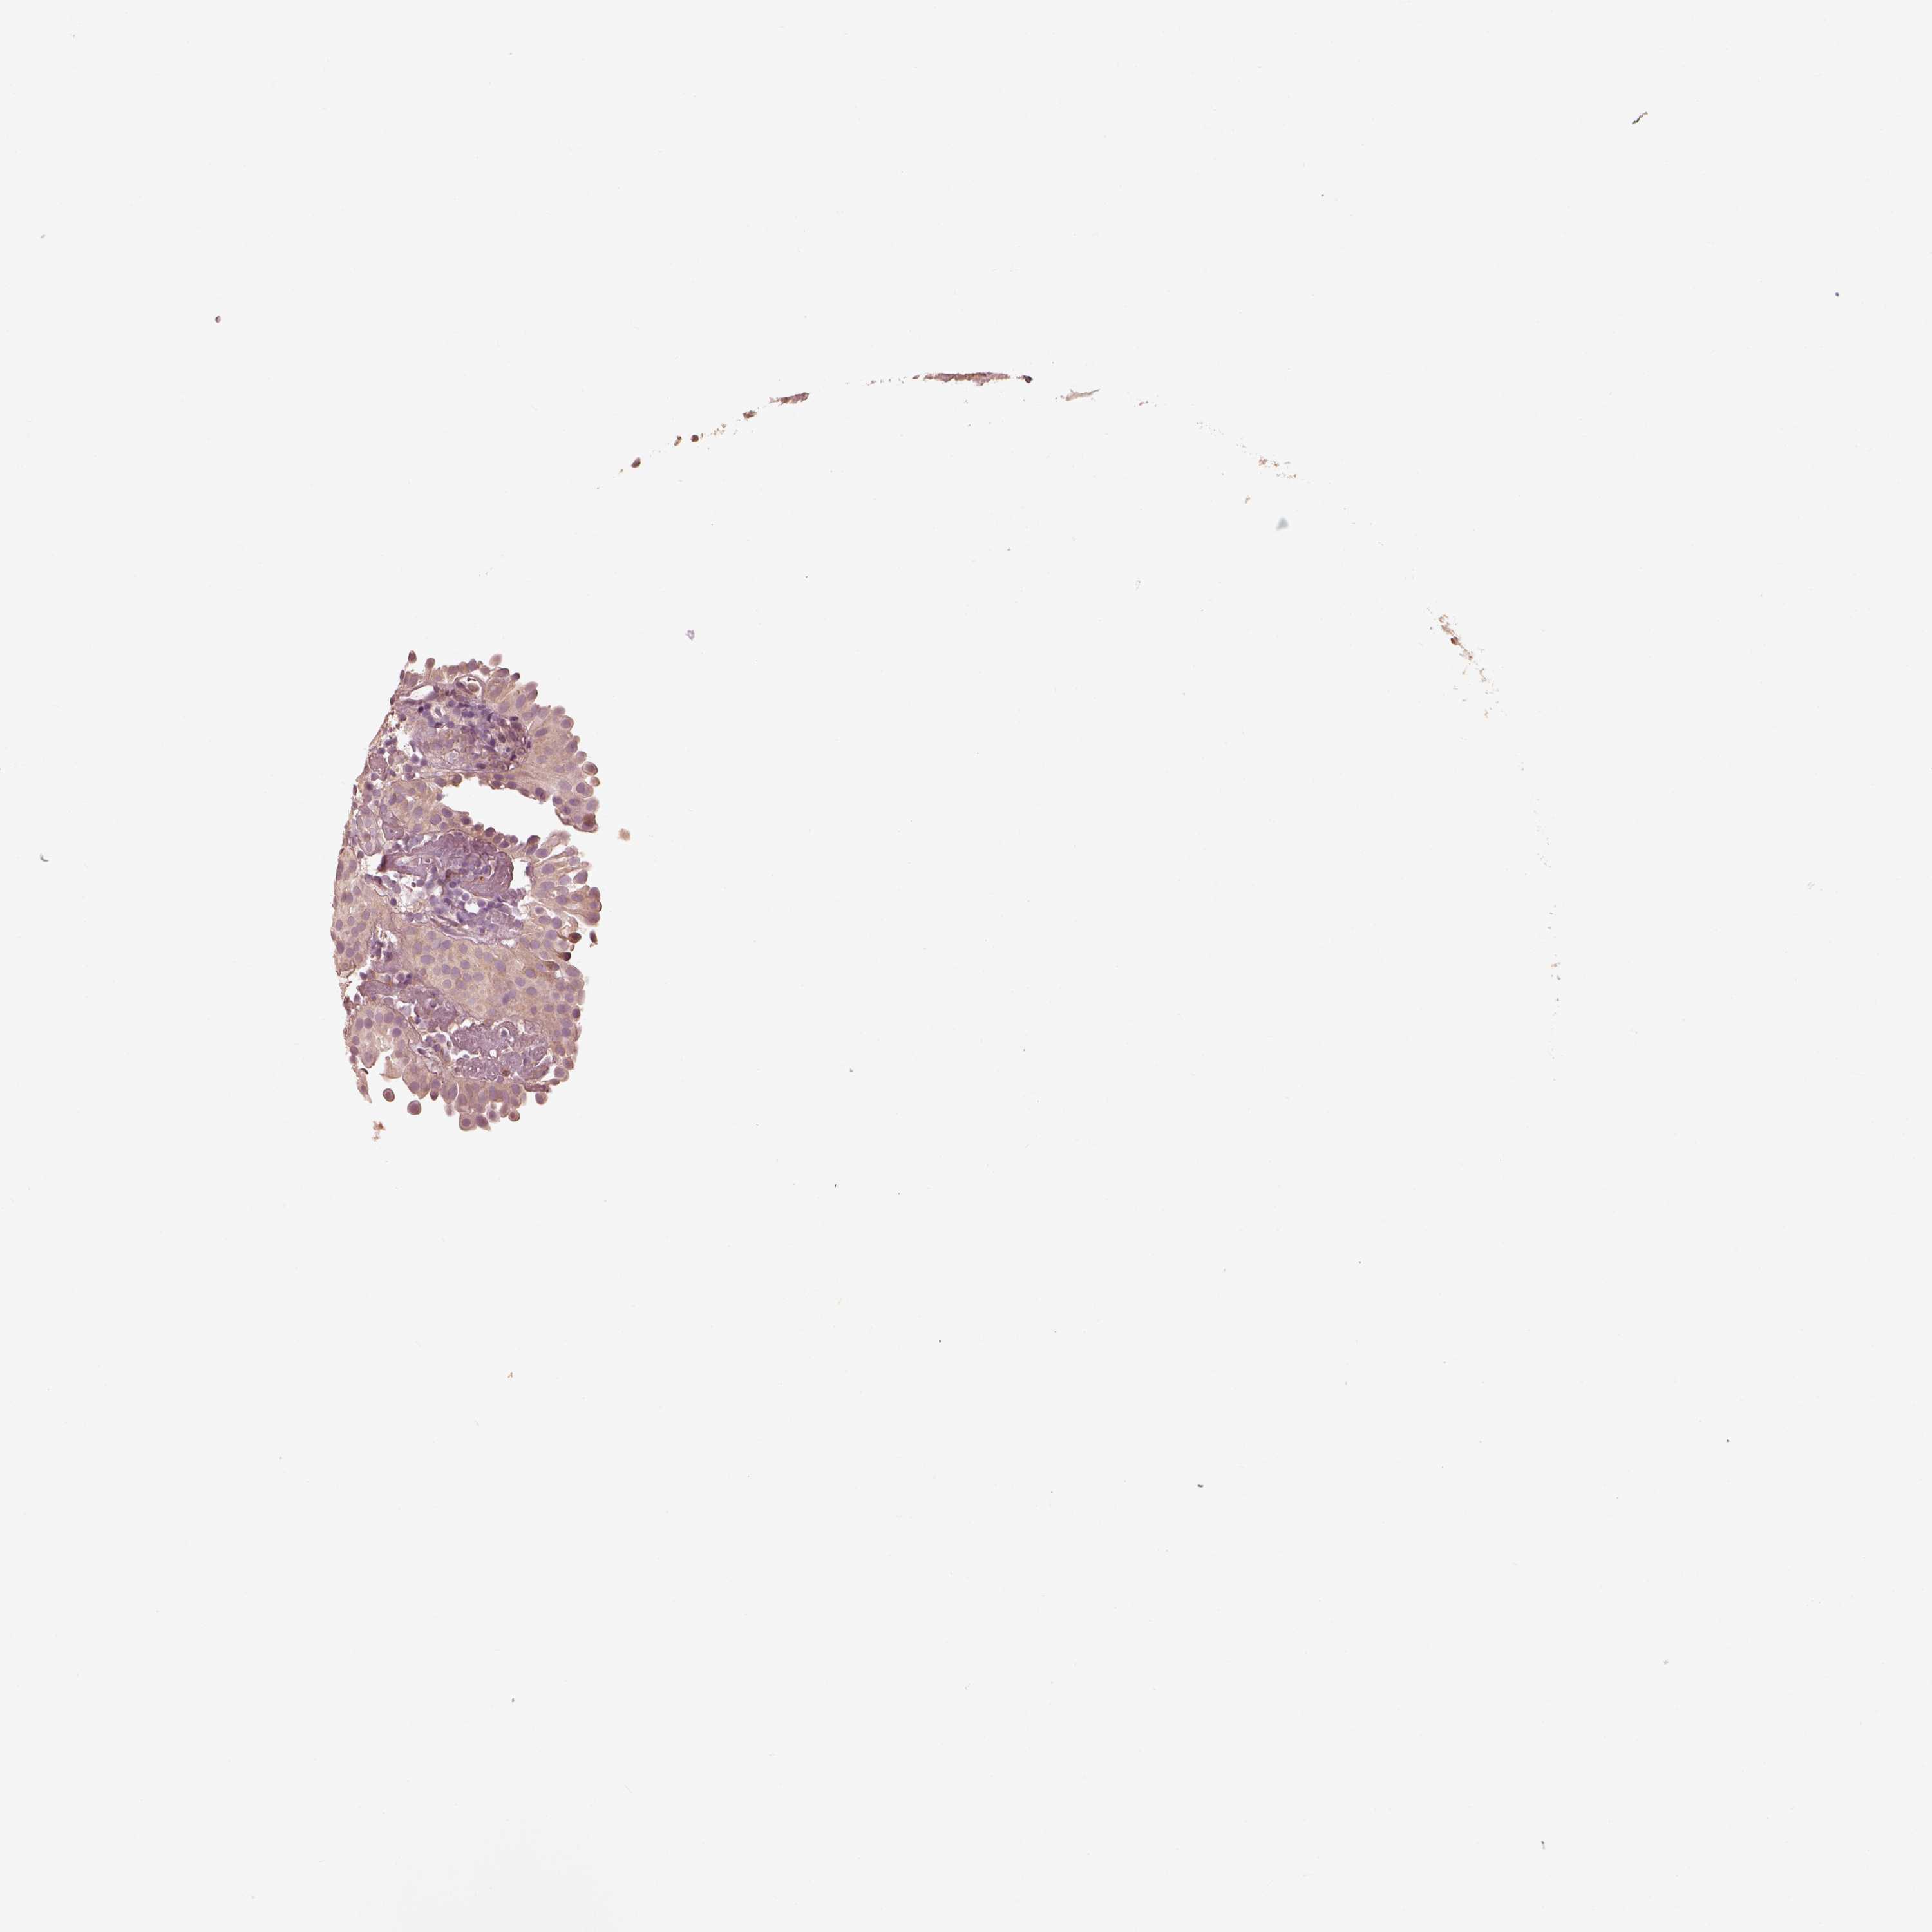

UROTHELIAL CANCER - Protein expressioni

A mouse-over function shows sample information and annotation data. Click on an image to view it in a full screen mode. Samples can be filtered based on level of antibody staining by selecting one or several of the following categories: high, medium, low and not detected. The assay and annotation is described here.

Antibody stainingi

Antibody staining in the annotated cell types in the current human tissue is reported as not detected, low, medium, or high, based on conventional immunohistochemistry profiling in selected tissues. This score is based on the combination of the staining intensity and fraction of stained cells.

Each image is clickable and will lead to virtual microscopy that enables deeper exploration of all samples and also displays staining intensity scores, fraction scores and subcellular localization as well as patient and tissue information for each sample.

Antibody HPA069520

Staining

High

Medium

Low

Not detected

Intensity

Strong

Moderate

Weak

Negative

Quantity

>75%

75%-25%

<25%

None

Location

Nuclear

Cytoplasmic/membranous

Cytoplasmic/membranous,nuclear

Urothelial carcinoma, High grade

Urothelial carcinoma, NOS

Urothelial carcinoma, Low grade